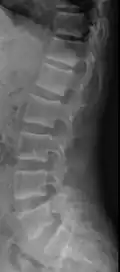

X-ray of a subtle "rugger jersey spine" due to sclerotic bands adjacent to the vertebral endplates.[18] -

CT scan of the same case.[18]